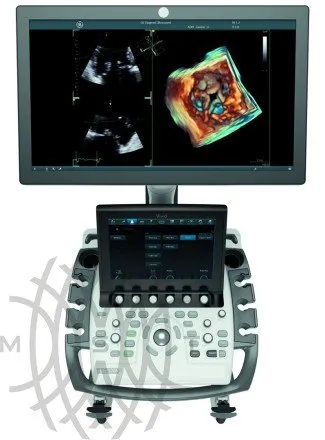

Ультразвуковой аппарат GE Vivid S70

- ЖК монитор 19″ на шарнирном кронштейне с датчиком освещенности

- Сенсорный цветной экран высокого разрешения диагональю 12.1″ с интерактивным меню

Высокая вычислительная мощность аппарата позволяет ему обрабатывать огромные наборы ультразвуковых данных, получая более достоверные и информативные результаты, что обеспечивает однородность при сканировании пациентов с разными типами телосложений. Богатый функционал системы, средства количественного анализа вкупе с простым и удобным рабочим процессом обеспечивают высокоэффективную и точную диагностику.

Компактный УЗИ аппарат экспертного класса Vivid S70 с поддержкой объемной чреспищеводной эхокардиографии — 4D TEE, поднимает диагностику заболеваний сердечно-сосудистой системы на новый уровень, позволяя сделать отделения кардиоваскулярной диагностики по-настоящему передовыми и современными.

Новый УЗИ аппарат Vivid S70, соединяя в единое целое экспертные технологии Vivid и ультрапроизводительную программную платформу формирователя луча и реконструкции изображений cSound, выводит ультразвуковые исследования на абсолютно иной уровень, посредством формирования изображений высочайшего качества как при диагностике сердечно-сосудистой системы, так и в других областях, и что немаловажно — по достаточно демократичной цене.

По сравнению с обычными системами новый Vivid S70 обладает на много большей вычислительной мощностью, что позволяет ему обрабатывать огромные наборы ультразвуковых данных, получая более достоверные и информативные результаты, что обеспечивает однородность при сканировании пациентов с разными типами телосложений. Богатый функционал системы, средства количественного анализа, невероятно простой и удобный рабочий процесс, обеспечивают высокоэффективную и точную диагностику.